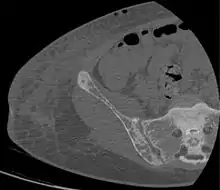

Renal osteodystrophy is usually diagnosed after treatment for end-stage kidney disease begins; however the CKD-MBD starts early in the course of CKD.[1][6] In advanced stages, blood tests will indicate decreased calcium and calcitriol (vitamin D) and increased phosphate, and parathyroid hormone levels. In earlier stages, serum calcium, phosphate levels are normal at the expense of high parathyroid hormone and fibroblast growth factor-23 levels. X-rays will also show bone features of renal osteodystrophy (subperiostic bone resorption, chondrocalcinosis at the knees and pubic symphysis, osteopenia and bone fractures) but may be difficult to differentiate from other conditions. Since the diagnosis of these bone abnormalities cannot be obtained correctly by current clinical, biochemical, and imaging methods (including measurement of bone-mineral density), bone biopsy has been, and still remains, the gold standard analysis for assessing the exact type of renal osteodystrophy.[6][16]